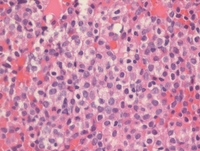

Bone core biopsy findings in APL

The H&E section of the bone core biopsy demonstrates sheets of monomorphic leukemic promyelocytes with abundant granular eosinophilic cytoplasm replacing most of the interstitial areas. CD117 immunostain is strongly positive in the leukemic promyelocytes.